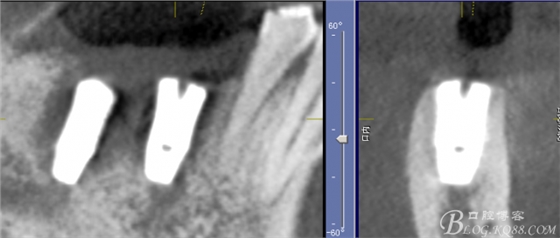

CT可見(jiàn)根管內(nèi)有白色顯影物和根周較大暗影

從根管影像看治療還是不錯(cuò)的,

懷疑牙根微裂,

三維檢查種植體位置,方向,平行度